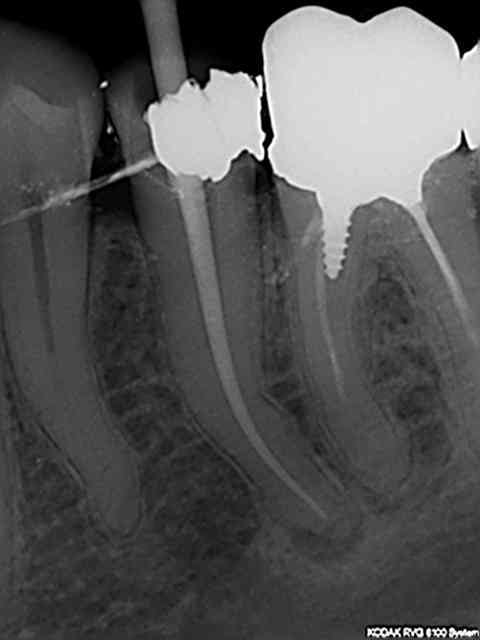

Une tuerie en rte, c'est plus facile. Exemple 33 tt canalaire incomplet pas trop pourri et pas de pèche. 10 mn chrono dont 7 d'irrigation-endo-activator. (c'est long 7 minutes !) Cone fondu au machtou vert et empreinte dans la séance 30 mn TTC empreinte- provisoire (auto moulage) posée.

R2 s2n3oe - Eugenol

R1 zpijyn - Eugenol

R3 jogwq3 - Eugenol